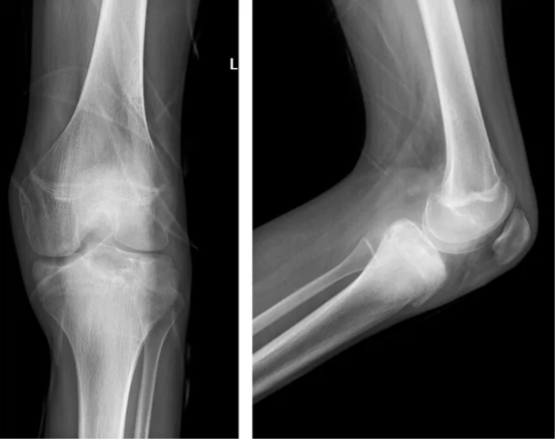

术后复片:左侧胫骨平台占位术后,内见高密度填充影,周围骨质内见隧道影。

术后1月复查:结合运动康复,患者膝关节屈曲畸形基本纠正。影像检查示左侧胫骨平台占位术后,内见高密度填充影,与周围骨质愈合较好。